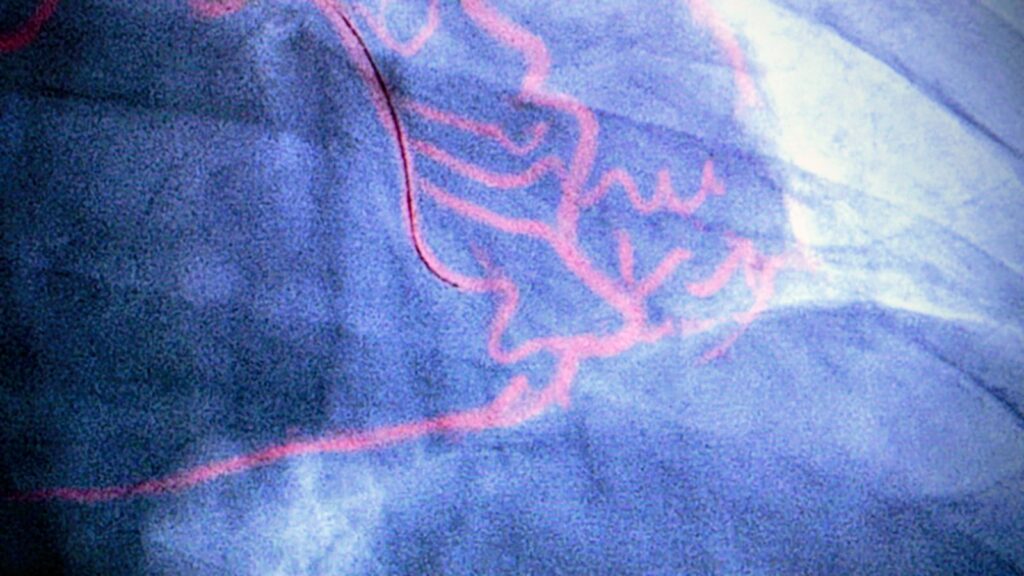

Оваа процедура всушност претставува примена на мапирање на коронарните артерии (coronary road mapping) со цел стентирање со употреба на минимално количество на контрастно средество.

Имено, најсовремениот ангиографски апарат PHILIPS AZURION 7 со кој е опремена нашата клиника, ја вклучува и оваа опција со што се овозможува стентирањето кај пациентите да биде извршено со минимално количество на контрастно средство и зрачење. Предноста на оваа метода е особено корисна за пациенти со хронична бубрежна инсуфициенција кај кои употребата на поголемо количество на контрасно средство може да доведе до акутно влошување на бубрежната инсуфициенција.

Со комбинација на прецизност, намалена употребa на контраст и зрачење, овие системи поставуваат нови стандарди за безбедност и ефикасност во катетеризационите лаборатории.